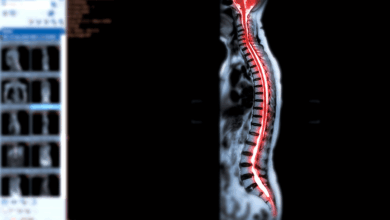

Cirurgia de Escoliose é Perigosa?

Como cirurgião ortopedista especialista em coluna vertebral, recebo frequentemente em meu consultório pacientes e familiares preocupados, querendo saber se a…